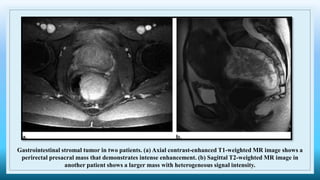

Gastrointestinal stromal tumor in two patients. (a) Axial contrast-enhanced T1-weighted MR image shows a

perirectal presacral mass that demonstrates intense enhancement. (b) Sagittal T2-weighted MR image in

another patient shows a larger mass with heterogeneous signal intensity.